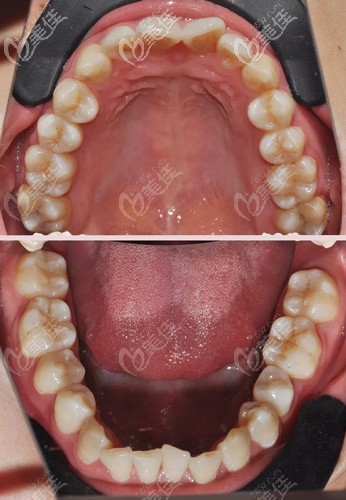

術(shù)前照片:

術(shù)后照片:

看見小護(hù)士這張術(shù)前照,能明顯的看出來牙齒不齊還有錢前凸,雖然不明顯,但小護(hù)士是比較高要求的。所以在找潘醫(yī)生面診后就決定用金屬托槽矯正(別問為什么,問就是窮),矯正后感覺牙齒一直有點(diǎn)酸疼,連張嘴吹個(gè)風(fēng)都不舒服,還有就是感覺嘴巴里有個(gè)異物,吐又吐不出來,很難受。

這是小護(hù)士到期去掉牙套時(shí)的照片留念,去牙套的時(shí)候她表示很不舒服的,感覺和戴牙套的疼痛一樣,畢竟也是用了一年多的東西,不過去掉牙套后發(fā)現(xiàn)牙齒整齊了不少,而且還變白了,整體的改善效果還是比較自然,不過去掉之后就直接戴起了保持器,畢竟還是要穩(wěn)定下牙齒的,不然很容易恢復(fù)到原來的樣子的。